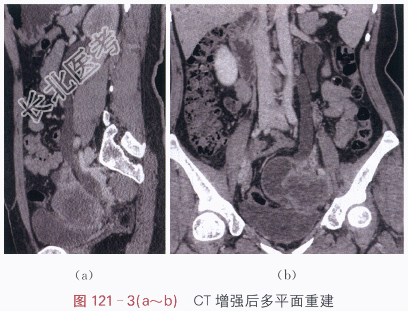

影像学资料如图121-1~图121-3所示。

读片分析:左侧附件区囊实性不规则形肿块,CT增强后实性部分的边缘呈明显强化,中心坏死部分强化不明显,未见肿大淋巴结和腹水征象。多平面重建后可见,左输尿管下段后累及,其中上段积水扩张。